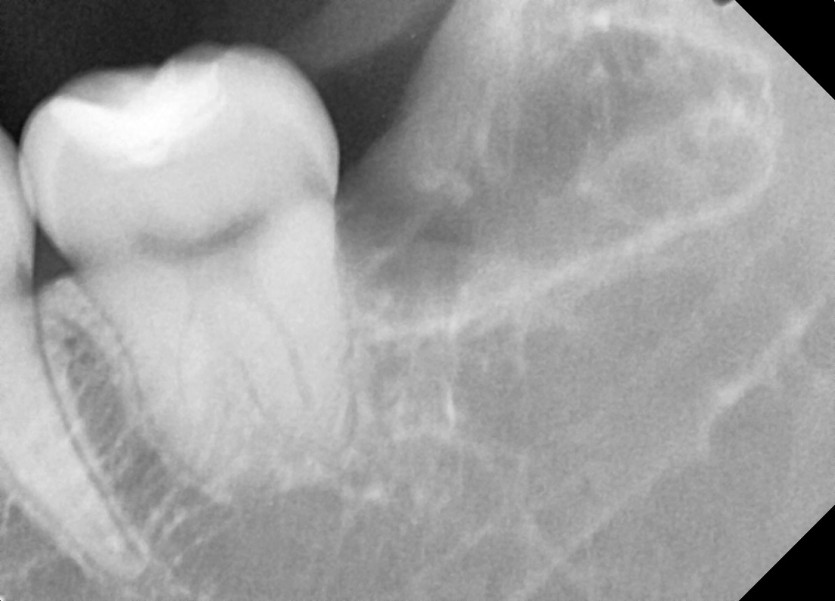

#38,48 사랑니 발치

구강 외과 전문의가 당일 발치했습니다.